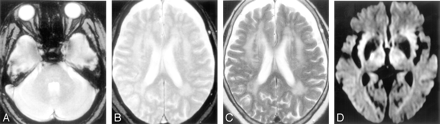

The mean follow-up period was 564.8 ± 220.5 days. Three patients were lost to follow-up (2 patients in group C and 1 patient in group D), and 1 patient in group B died of a cause not related to stroke. During the follow-up period, 26 patients developed recurrent strokes, including 10 intracerebral hemorrhages and 16 ischemic strokes. Representative MR and CT images of patients with recurrent stroke are shown in Figs 1 and 2. Frequencies of the development of overall recurrent stroke, intracerebral hemorrhage, and ischemic stroke are shown in Table 2, Table 3, and Table 4, respectively. Development of intracerebral hemorrhage was the most frequently observed in patients of group D (19.0%). Analysis by the Kaplan-Meier method showed that the estimated recurrence rate of intracerebral hemorrhage was also the highest in patients in group D. The frequency of development of ischemic stroke was the highest in patients in group A (15.4%), followed by patients in group B (9.6%) and patients in group C (3.8%), whereas no patients in group D developed ischemic stroke. Patients in group A also showed the highest estimated recurrence rate of ischemic stroke in the 4 groups.

MR and CT images obtained from a patient (70-year-old man) with intracerebral hemorrhage in the cerebellum, who had been treated with aspirin after the occurrence of lacunar infarction. A and B, Initial T2*-weighted gradient-echo images (TR/TE, 800/26; flip angle, 20°) show multiple microbleeds in the brain stem, cerebellum, basal ganglia, and cerebral hemispheres. C and D, T2-weighted spin-echo images (TR/TE, 4500/112) do not show advanced white matter hyperintensity. E and F, CT image (E) and T2*-weighted gradient-echo image (F) obtained 9 months after the lacunar infarction show occurrence of cerebellar hemorrhage.